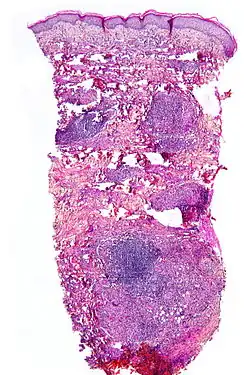

Histopathology

Although the exact cause of this condition is not known, it is an inflammatory disorder characterized by collagen degeneration, combined with a granulomatous response. It always involves the dermis diffusely, and sometimes also involves the deeper fat layer. Commonly, dermal blood vessels are thickened (Microangiopathy).[21]

Diagnosis

NL is diagnosed by a skin biopsy, demonstrating superficial and deep perivascular and interstitial mixed inflammatory cell infiltrate (including lymphocytes, plasma cells, mononucleated and multinucleated histocytes, and eosinophils) in the dermis and subcutis, as well as necrotising vasculitis with adjacent necrobiosis and necrosis of adnexal structures.[23] Areas of necrobiosis are often more extensive and less well defined than in granuloma annulare. The presence of lipid in necrobiotic areas may be demonstrated by Sudan stains. Cholesterol clefts, fibrin, and mucin may also be present in areas of necrobiosis. Depending on the severity of the necrobiosis, certain cell types may be more predominant. When a lesion is in its early stages, neutrophils may be present, whereas in later stages of development, lymphocytes and histiocytes may be predominant.[24]